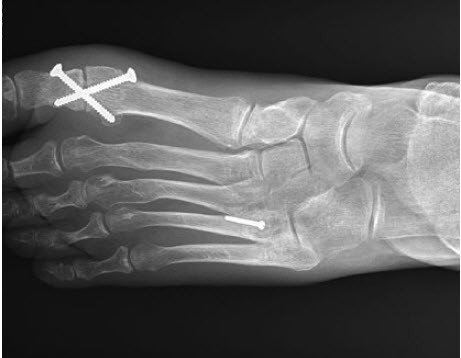

Pseudarthrose

Pseudarthrose ist der Fachbegriff für eine verzögerte oder fehlende Knochenheilung nach einem Knochenbruch. Auch nach Versteifungs- oder Korrekturoperationen kann die Knochenheilung ausbleiben. Die Stosswellentherapie regt die Bildung frischer Knochenzellen an, wodurch sie in den Spalt einwandern und sich vermehren können. In vielen Fällen, vor allem im Mittel- und Vorfussbereich, kann der instabile Knochen so geheilt werden.